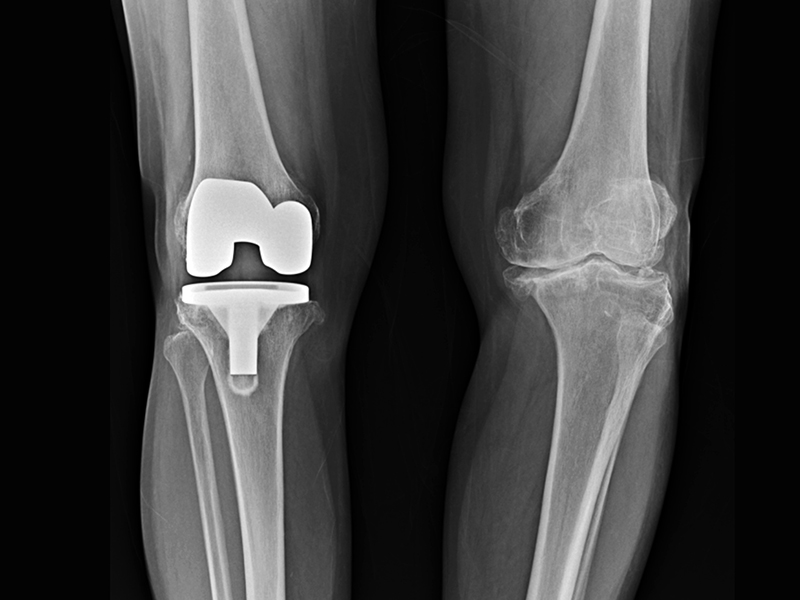

The range of potential applications is enormous. However, two are particularly promising: firstly, the new process can be used to create special biomedical coatings. For example, implants can be coated in such a way that they are not only antibacterial, but also have a growth-stimulating effect on the bone.